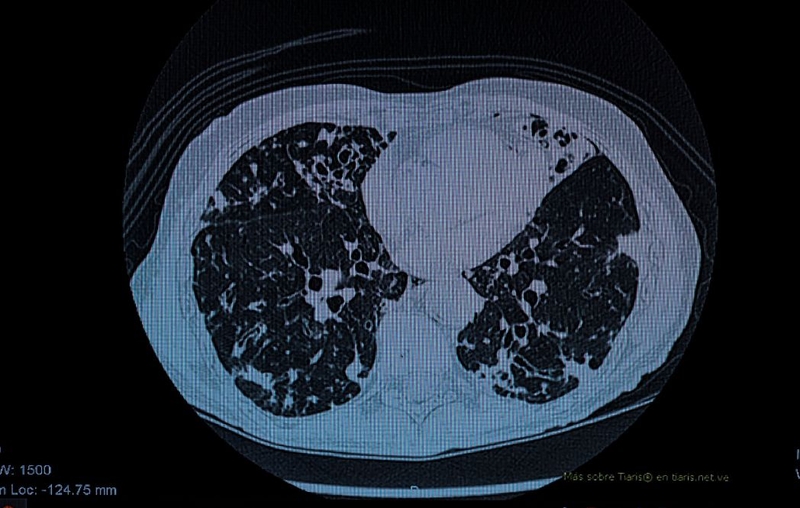

Giãn phế quản là tình trạng các phế quản, đường dẫn khí trong phổi bị giãn rộng và mất đi tính đàn hồi tự nhiên. Điều này tạo ra những "túi" nhỏ trong phế quản, nơi dịch nhầy và vi khuẩn dễ dàng tích tụ, gây viêm nhiễm và khó khăn trong việc tống xuất đờm. Khi hệ thống miễn dịch của phổi bị suy yếu do giãn phế quản, vi khuẩn có cơ hội xâm nhập và gây ra nhiễm trùng thứ phát, gọi là bội nhiễm.

Sự giãn nở của phế quản tạo điều kiện cho vi khuẩn phát triển, gây nhiễm trùng và làm tổn thương phế quản thêm, từ đó lại làm nặng thêm tình trạng giãn phế quản. Theo một nghiên cứu được công bố trên tạp chí European Respiratory Journal, bệnh nhân giãn phế quản có nguy cơ bội nhiễm cao gấp 4 lần so với người bình thường. Giãn phế quản bội nhiễm là một biến chứng nguy hiểm của bệnh giãn phế quản, gây ra nhiều khó khăn trong điều trị và ảnh hưởng nghiêm trọng đến chất lượng cuộc sống của người bệnh.